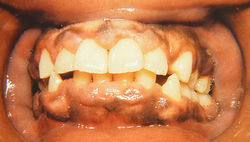

Фенитон, циклоспорин и блокаторы кальциевых каналов могут вызвать гиперплазию десен (рис. 23.6). Она развивается у 40% пациентов, принимающих фенитон. Среди блокаторов кальциевых каналов исрадипин обладает наименьшей вероятностью индукции гиперплазии десен. Слизистая оболочка десен начинает набухать и покрывает зубы. В тяжелых случаях гипертрофированная слизистая оболочка полностью закрывает зубы, что требует хирургического вмешательства.

Рис. 23.6 Лекарственная гиперплазия десен. Сосочки десен проявляют умеренную гиперплазию, связанную с применением фенитона. Внимание к гигиене полости рта и рутинное удаление зубных камней для контролирования местных факторов позволяет снизить тяжесть гиперплазии. Похожую гиперплазию вызывают циклоспорин и антагонисты ионов кальция.